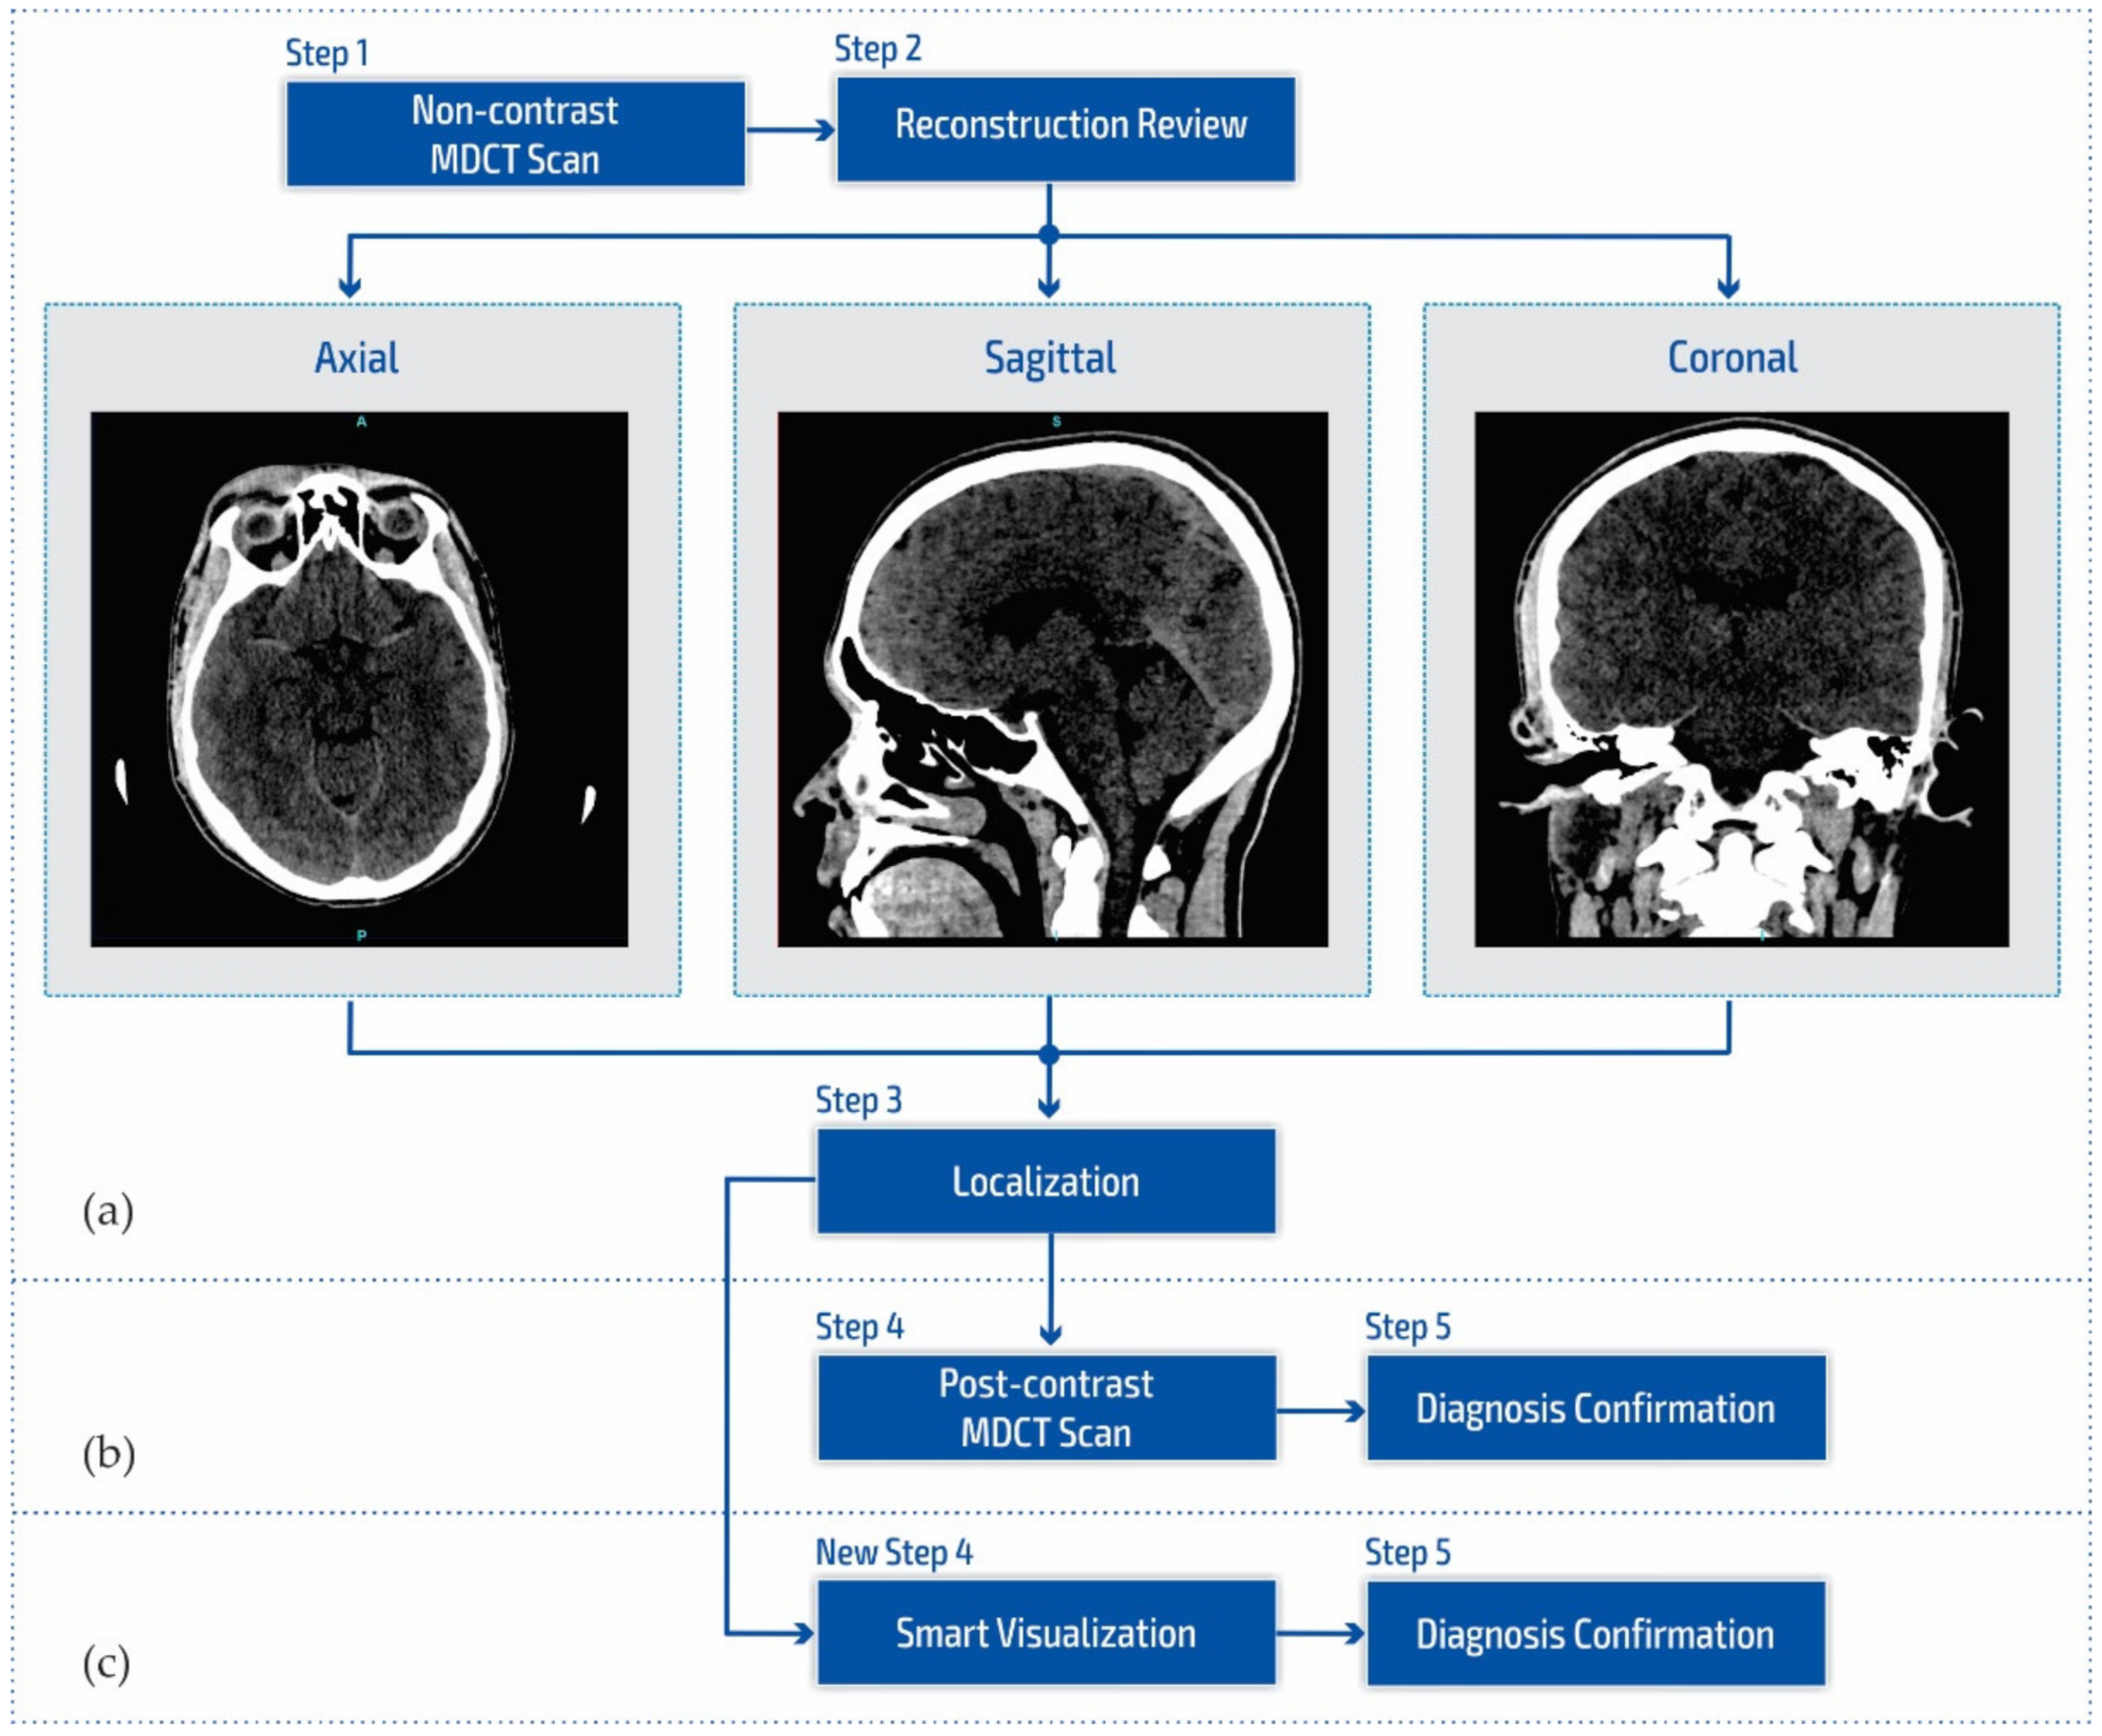

In our research approach, in marking content and regions of interest all values that do not contribute to the content are set to a pixel value of zero. In this way, the levels of black (which have a value of zero or slightly greater than zero), white values (which have a maximum value), and values of gray that are not contained in the central part of the gray are set to zero so as not to interfere with the physician conclusion while observing the central segment. At the same time, white parts (for example, bones) do not affect the mean value of the observed part. The smart visualization and the summary of the system output of the developed SVMI model is shown in Figure 3.

Figure 3.

Summary of the system outputs.

After determining the localization of the appropriate level of a particular cross-section by an experienced neuroradiologist, centering and masking of contents and regions of interest are performed. For a non-contrast MDCT scan in a DICOM-standardized format file, in which integers represent all pixels, it is necessary to extract useful information. Therefore, only the gray range is observed so that all gray values are less than a particular value, all values greater than the other selected value are observed, and all are set to zero so as not to affect the mean value of the selected segment. Adjacent pixel values are colorized differently, meaning that physicians do not need to recognize close levels of gray because segments that have similar pixel values are different. By masking this content, a specific part can be selected (above, below, left and right 1/3, or 2/3 vertically and horizontally) so that only the part of interest is magnified. On the right, relative values of gray from zero to one are provided with a label that shows the color. The minimum and maximum values are chosen arbitrarily so that only the range of gray is observed. All other values are zero and do not affect the mean and standard deviation. Assigned colors can be changed according to the physician’s preferences to provide a clearer view of image segments with the same pixel value. The mean and variance are calculated for the selected range. It is also possible to perform averaging so that the close ranges are more clearly separated from the rest of the pixels.

(a) Non-contrast MDCT image of the endocranium; (b) SVMI of the non-contrast MDCT image of the endocranium; and (c) MDCT perfusion of the same cross-section.

Figure 13a shows a non-contrast MDCT image of the endocranium establishing a zone of hypodensity without clear differentiation of the gray–white mass on the occipital right, which corresponds to an acute ischemic lesion. Figure 13b presents our method of smart visualization of the medical images (SVMI) of the non-contrast MDCT image of the endocranium of the same cross-section. Figure 13c, after additional diagnostics of MDCT perfusion, shows a perfusion deficit that can be seen in the same region—occipital right—which confirms the diagnosis of an acute ischemic stroke.

On the presented non-contrast MDCT image of the patient’s endocranium (Figure 13a), 100% (nine) of radiology specialists noticed that changes in the brain had occurred based on their knowledge in the field of neuroradiology, which ranged from 3 to 15 years of experience for all radiologists who expressed their expert opinion. On the other hand, based on the non-contrast MDCT image of the endocranium (Figure 13a), 81.81% (nine) of the total number of MDs in the radiology residency training program who participated in the questionnaire did not notice the change, did not adequately characterize it, or did not give an adequate differential diagnosis. Table 1 shows the analysis of the physicians’ answers to the first question observing only Figure 13a.

Following smart visualization (SVMI) of the non-contrast MDCT image of the endocranium (Figure 13b), out of all physicians whose opinions were requested, 95% of respondents made an accurate diagnosis and confirmed the existence of pathological changes in density. However, one MD in a radiology residency training program answered incorrectly. Table 2 shows the analysis of the physicians’ answers to the second question observing only Figure 13b.